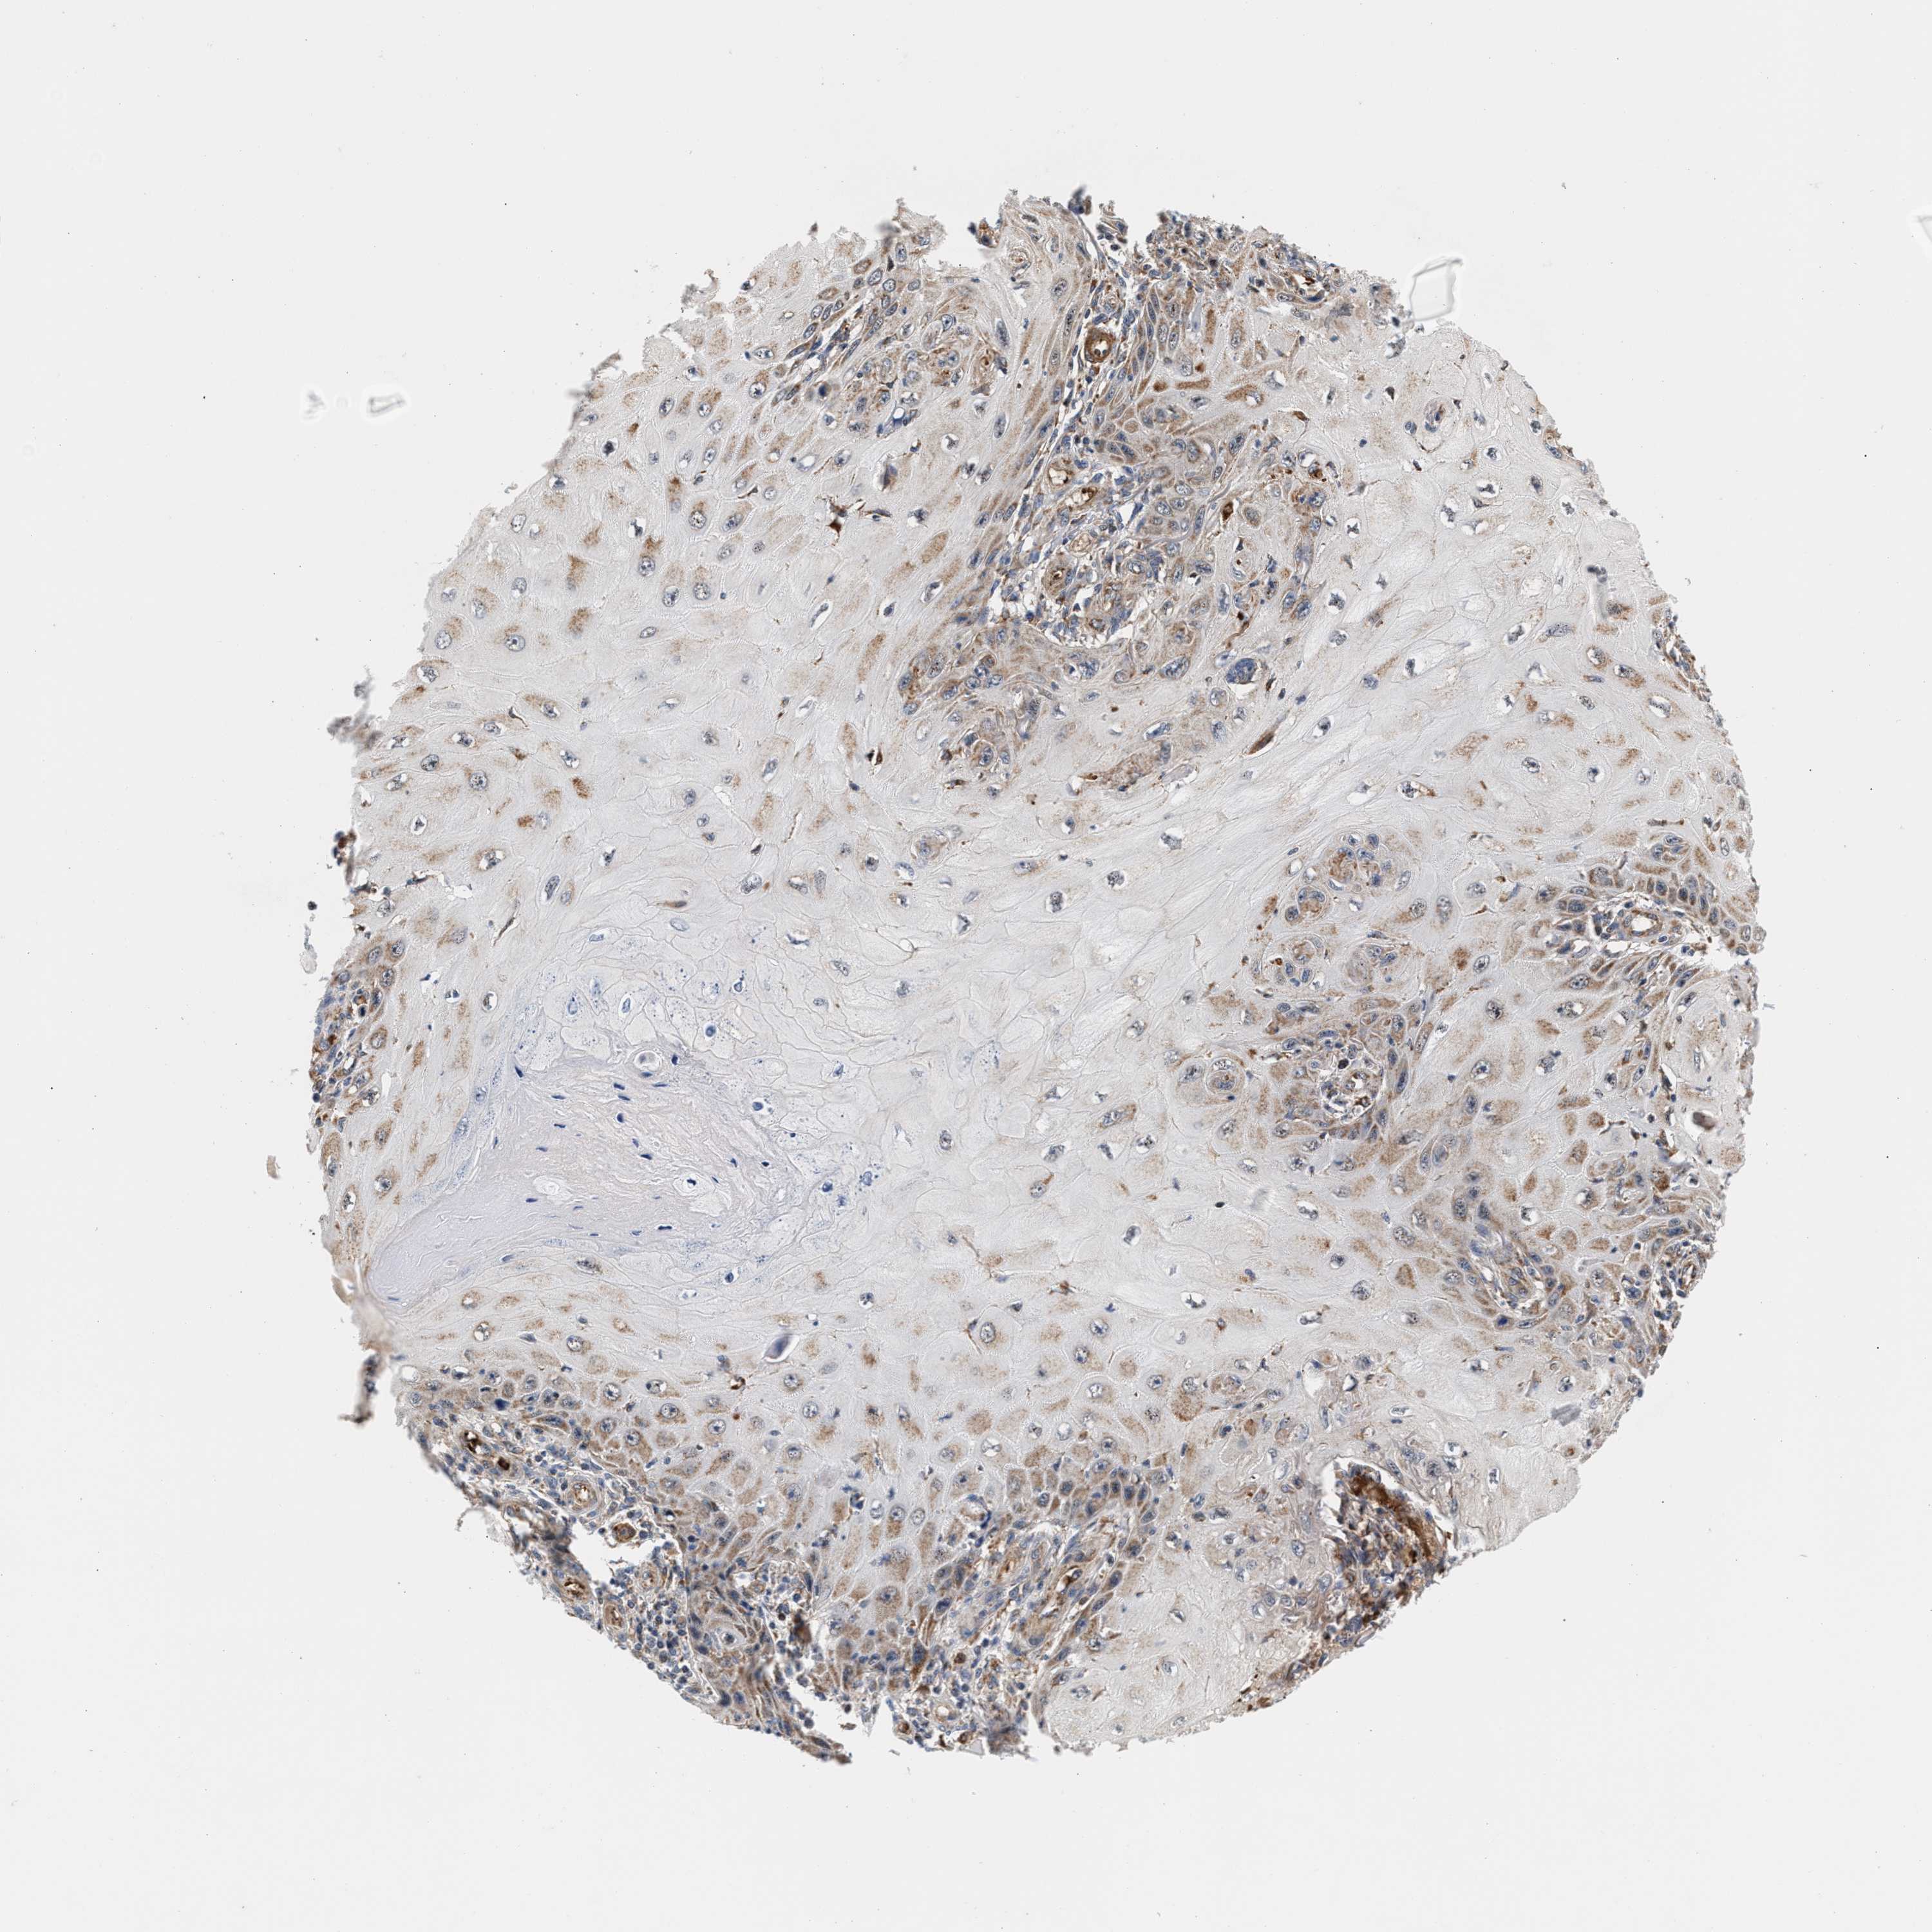

SKIN CANCER - Protein expressioni

A mouse-over function shows sample information and annotation data. Click on an image to view it in a full screen mode. Samples can be filtered based on level of antibody staining by selecting one or several of the following categories: high, medium, low and not detected. The assay and annotation is described here.

Each image is clickable and will lead to virtual microscopy that enables deeper exploration of all samples and also displays staining intensity scores, fraction scores and subcellular localization as well as patient and tissue information for each sample.

Antibody CAB022085

Staining

High

Medium

Squamous cell carcinoma, NOS